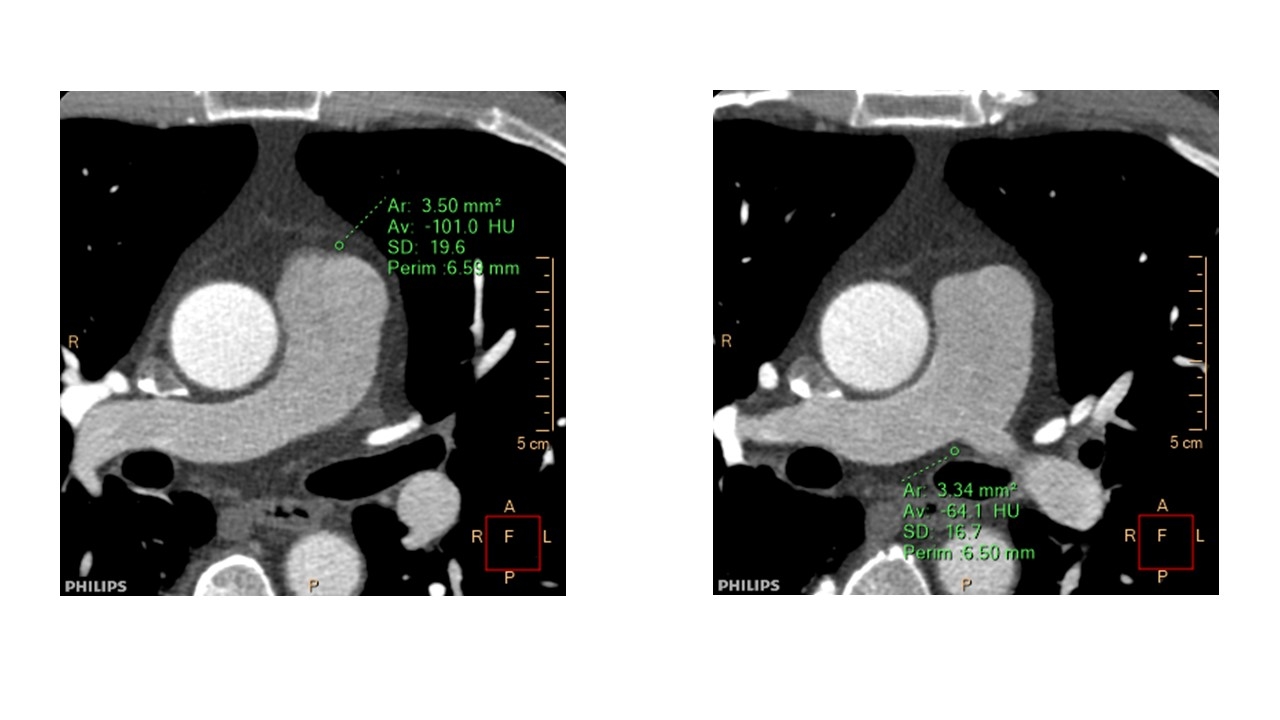

Methods: This is a retrospective analysis of 20 patients (7 male, mean age 54 year old) who underwent dual energy CT (7500, Philips) because of clinically suspected coronary artery diseases, but no significant stenosis in the coronary arteries on CT, and with normal ECG and transthoracic echocardiogram findings. From non-contrast and contrast data, EANs and EDs (% electron density relative to water) of peri-PA adipose tissue were determined at two sites in each patient as represented in Figure 1. We compared tricuspid regurgitation pressure gradient (mmHg).

Results: Mean EANs, and EDs of peri-PA adipose tissue at corresponding sites, were 6.15, and 6.52 (EANs), and 93.2 and 94.9 at in site 1 and 2, respectively in non-contrast phase, and 6.32, and 6.82 (EANs) in site 1 and 2, respectively in early phase. Correlation coefficients of each EAN and ED against tricuspid regurgitation pressure gradient on transthoracic echocardiogram were -0.04 and -0.13 (EANs), and 0.10 and 0.01 at in site 1 and 2, respectively in non-contrast phase, and -0.18 and -0.02 (EANs), and 0.18 and -0.24 at in site 1 and 2, respectively in early phase (Figure 2 and 3).